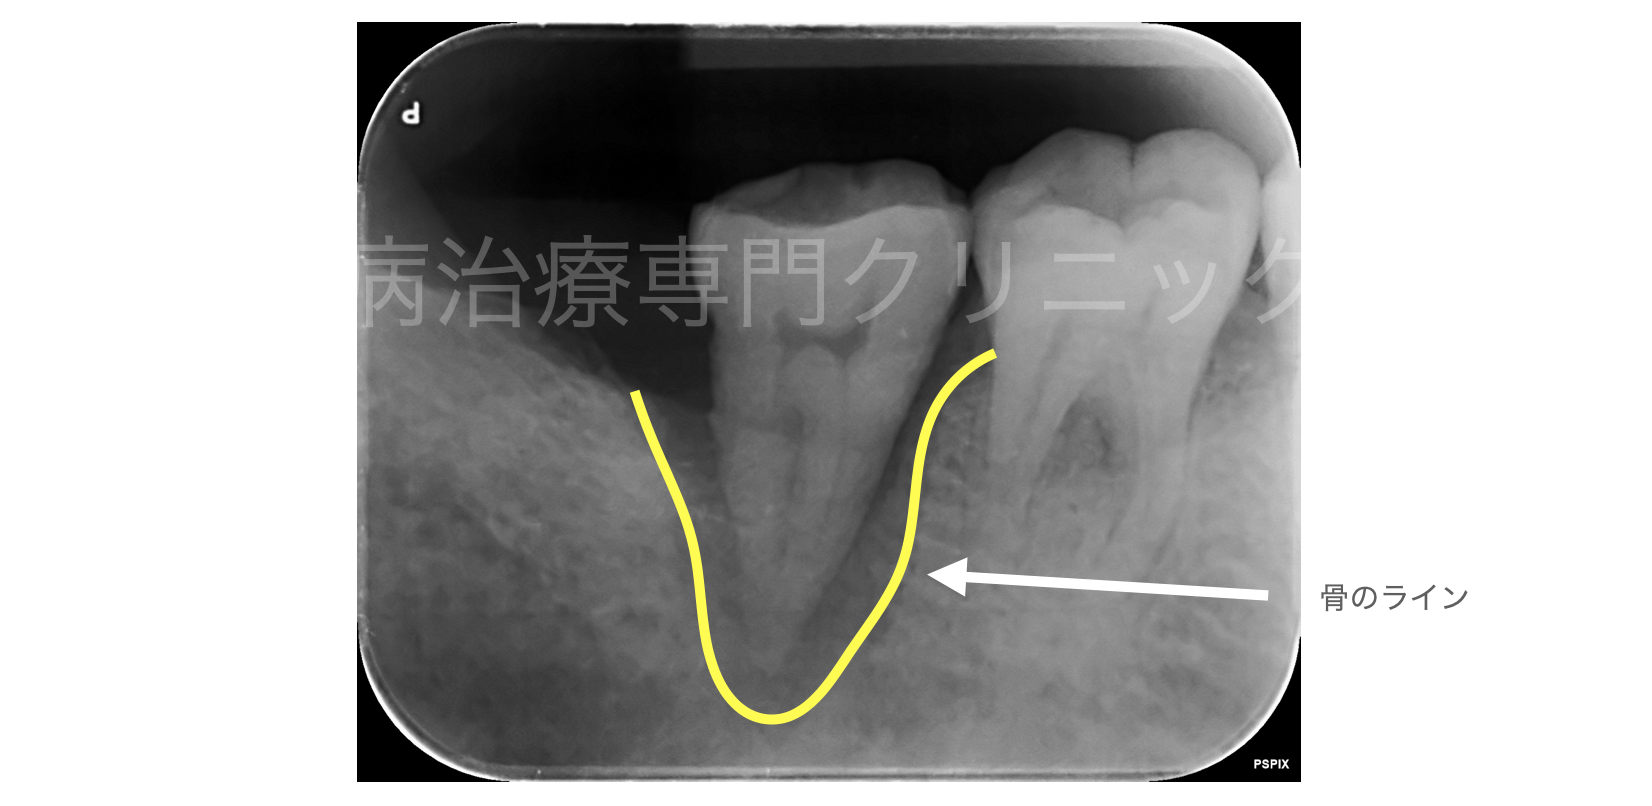

2018年6月21日に、米国歯周病学会、ヨーロッパ歯周病学会から、20年ぶりとなる、歯周病の新診断に ...